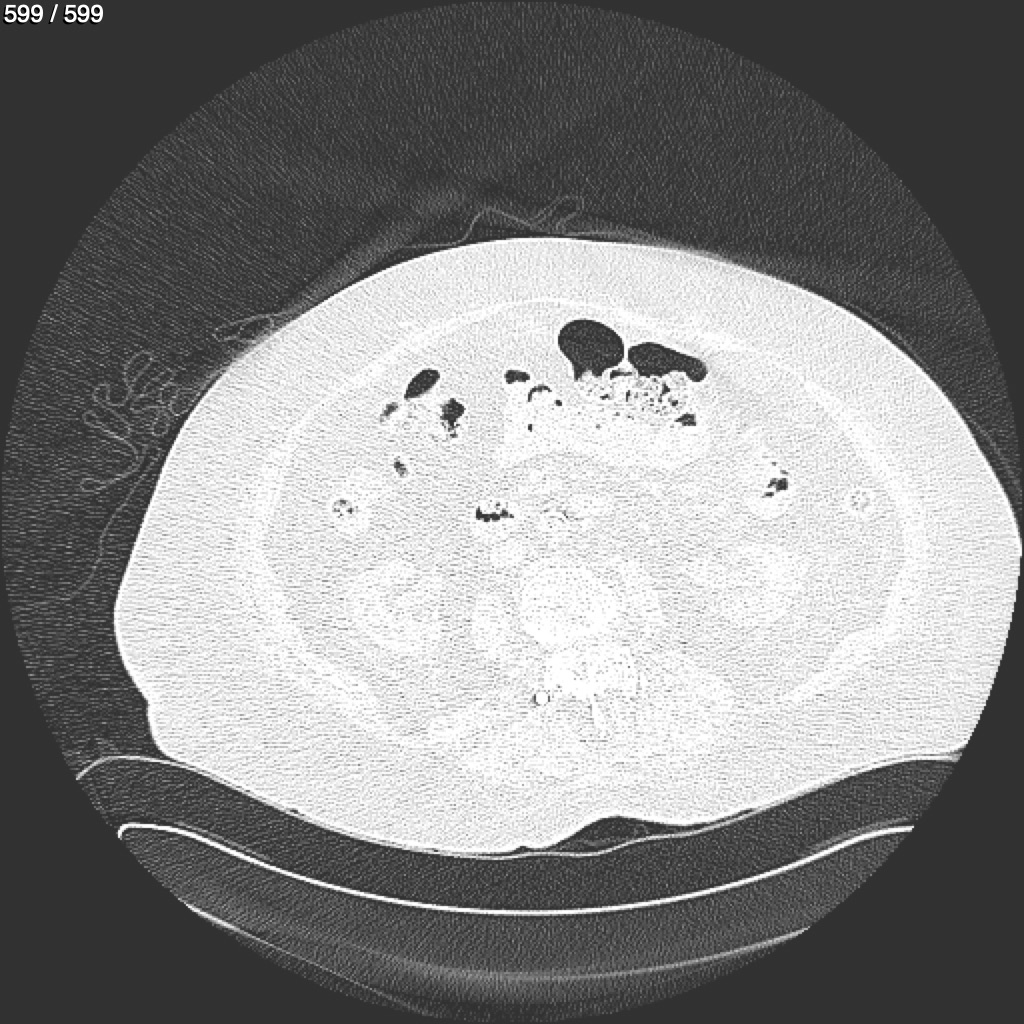

Home G​l​o​r​i​a​ ​G​l​a​d​y​s​ ​B​e​a​s​l​e​y​ ​-​ ​T​ó​r​a​x​ ​T​o​r​a​x​_​S​i​m​p​l​e​ ​(​A​d​u​l​t​o​)